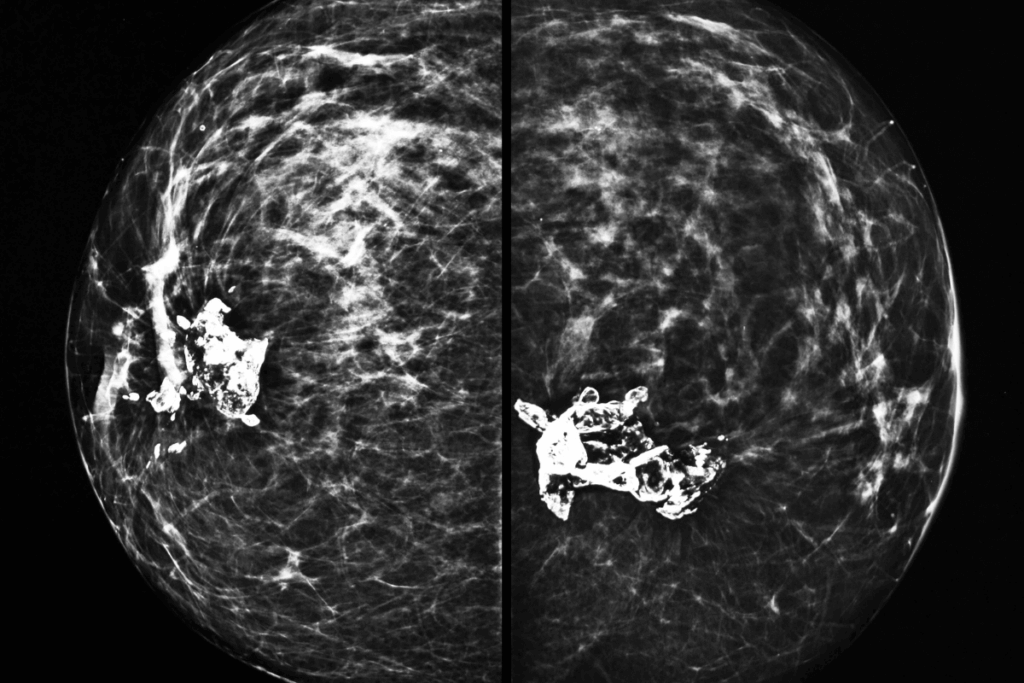

This retrospective cohort study included a total of 74,124 women (mean age = 55.5±10.4 years) from Emory Healthcare as an internal cohort and 49,638 women (mean age = 59.5±10.2 years) from Mayo Clinic as an external validation cohort. Only one index mammogram per patient was analyzed. Women with prior CVD, major adverse CVD events, and previous coronary imaging were excluded from this study. BAC was quantified by using a transform-based artificial intelligence (AI) model, which was applied to mediolateral oblique mammogram images. BAC severity was classified as severe (n = 714; mean age = 67.8±9.1 years), mild (n = 10,369; mean age = 58.9±10.9 years), none (n = 62,187; mean age = 54.6±10 years), or moderate (n = 854; mean age = 68.4±8.6 years). The median follow-up period was found to be 7 years (interquartile range [IQR]: 4-10). Major adverse cardiovascular events (MACE) and risk factors were detected from electronic health records (EHR). PREVENT risk scores were estimated in comparison with BAC measurements.

BAC was observed in 26% of women in the external cohort and 16.1% in the internal cohort. In the internal cohort, the incidence of MACE increased more than 8-fold from 5.96/1000 person-years in women with zero BAC to 48.89 in those with severe BAC. These event rates were consistently higher in the external cohort. BAC severity was strongly associated with cardiometabolic risk factors and age, with women with severe BAC being about 13 years older compared to those without BAC (p <0.001). Higher systolic blood pressure, diabetes, lower estimated glomerular filtration rate, higher body mass index, and use of statin and antihypertensive were also linked with increasing BAC severity, whereas smoking showed no association.